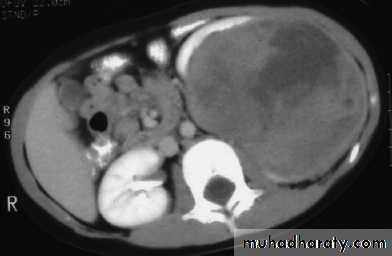

Ct enhanced

Big simple renal cyst(non enhancing mass homogenous) treatment is conservative or drainge if symptomaticWhat's the Diagnosis?